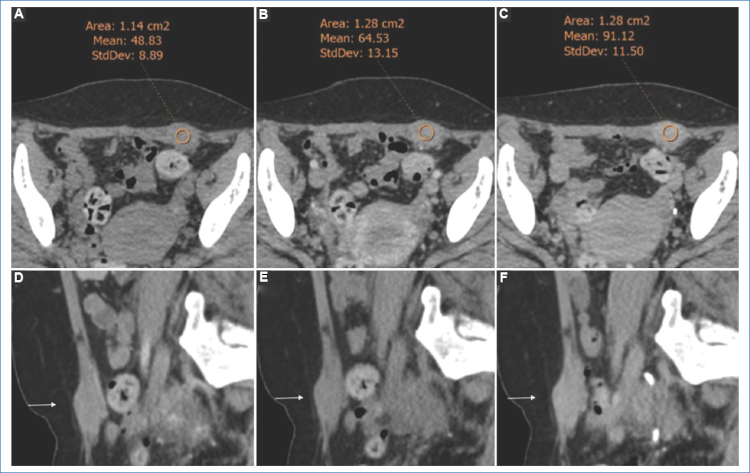

El rol fundamental de las imágenes es la valoración prequirúrgica y la determinación de la extensión regional de la lesión, siendo la ecografía transvaginal y la resonancia magnética (RM) los métodos utilizados para el estudio de la endometriosis profunda como la afectación de los espacios subperitoneales1. La apariencia de la endometriosis cicatrizal en la pared abdominal es variable y dependerá de la fase del ciclo menstrual, la cronicidad y la cantidad de elementos estromales o glandulares. Por RM, la formación suele ser hiperintensa y heterogénea en T1 y T2, como resultado de hemorragia subaguda en las criptas endometriales, aunque esto puede variar1. Por tomografía computada (TC) se observa como una formación nodular de densidad de partes blandas en relación a la cicatriz de cesárea, puede ser levemente hiperdensa con respecto al músculo y realza moderadamente con el contraste endovenoso.

Presentamos el caso de una paciente de 37 años, con antecedentes de cesárea (G1P0C1) dos años atrás, que consulta por una masa palpable no móvil en la pared abdominal anterior, en situación parasagital izquierda, en relación a una cicatriz de cesárea, de un año de evolución. La masa presentaba pequeño tamaño y se asociaba a dolor cíclico que aumentaba durante la menstruación, disminuyendo en los días intermenstruales. No se revelaron otros antecedentes de importancia al momento de la consulta. El médico derivante ordenó una TC abdominopélvica con contraste oral y endovenoso, que demostró la presencia de una imagen nodular con realce luego de la administración de contraste endovenoso en el espesor del músculo recto anterior izquierdo del abdomen, sin compromiso de la cavidad abdominal (Fig. 1). Debido a los hallazgos evidenciados y los antecedentes ginecológicos (cesárea previa y aumento del dolor en el ciclo menstrual), la probabilidad era muy alta para enfermedad endometrial, por lo que se descartó proseguir con otros estudios imagenológicos10 y se solicitó una punción-biopsia guiada por ecografía (Fig. 2). Este procedimiento se llevó a cabo utilizando un transductor lineal de 7.5 MHz (ecógrafo Esaote MyLab Twice) y una aguja Franseen de 20 G. La biopsia, mediante estudio citológico e histológico, confirmó el diagnóstico de endometriosis (Fig. 3).